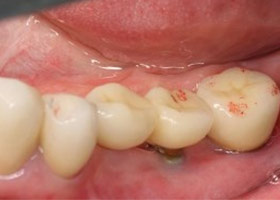

10. 假牙完成,病患恢復健康的角質化牙齦。